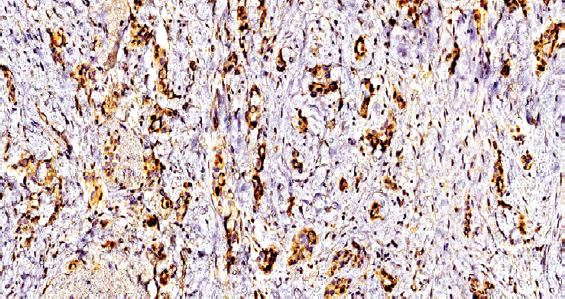

При иммуногистохимическом исследовании материала обнаружена достаточно распространенная экспрессия anti-BLV в различных структурах ткани РМЖ (рис. 1). Продукт реакции определялся в виде зерен и глыбок на поверхности клеточной мембраны, с преобладанием локализации в цитоплазме опухолевых клеток. Выявлена выраженная экспрессия данного вируса на стенке микрососудов (рис. 2). Обратило на себя внимание, что из четырех исследуемых групп экспрессия BLV наблюдалась только в случаях тройного негативного РМЖ (табл. 1).

Рис. 1. Экспрессия антигена вируса лейкоза коров в ткани рака молочной железы, увеличение в 200 раз; иммуногистохимическая окраска

Fig. 1. Expression of cow leukosis virus antigen in breast cancer tissue, zoom in 200; immunohistochemical staining

Опухолевые клетки, содержащие anti-BLV, выявлялись как вблизи так и на отдалении от сосудов микроциркуляторного русла. Можно было также наблюдать, что в опухолях, экспрессирующих anti-BLV, большее количество микрососудов, чем в срезах, с отрицательным результатом в этой же группе. Оценка этих препаратов при окраске гематоксилином и эозином показала низкодифференцированную аденокарциному молочной железы со значительной утратой тканевой органоспецифичности, преобладанием стромального компонента, полиморфными гиперхромными ядрами, большим количеством полнокровных микрососудов и высокой митотической активностью опухолевых клеток.